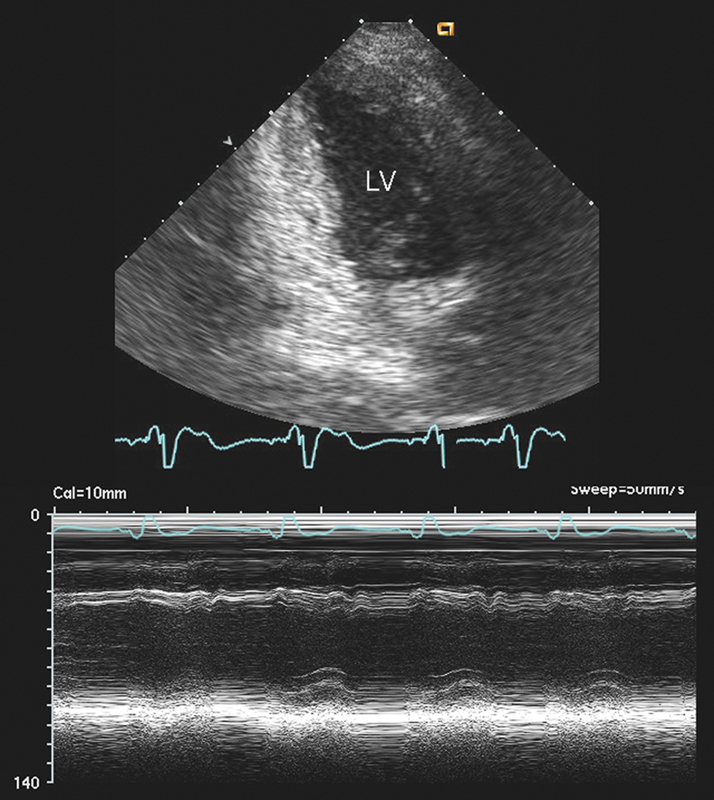

فحوصات تشخيصية لبعض امراض القلب والشرايين التاجية